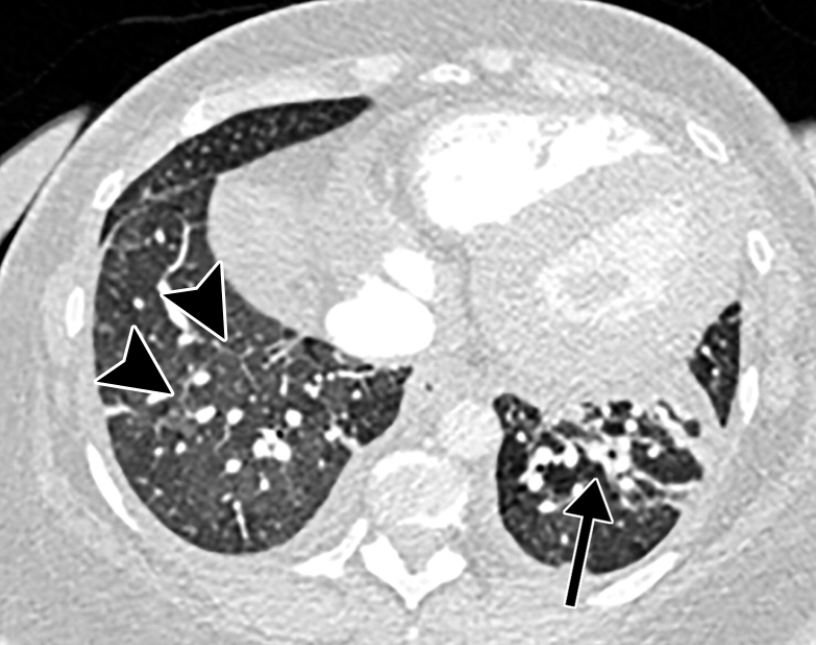

This photo gallery shows the variety of radiological presentations of COVID-19 (SARS-CoV-2) in medical imaging, including computed tomography (CT), radiograph X-rays, ultrasound, echocardiograms and magnetic resonance imaging (MRI). The radiology images show examples of typical COVID pneumonia in the lungs and the numerous complications the virus causes in the body in multiple organs, including the brain, kidneys, heart, abdomen and vascular system.

Ultrasound, especially hand-held ultrasound imaging devices, have become a primary imaging modality for novel coronavirus because of the ease to bag the device and sterilize it after use. CT and mobile X-ray systems are also used as front-line imaging systems for COVID-positive or suspected COVID patients.